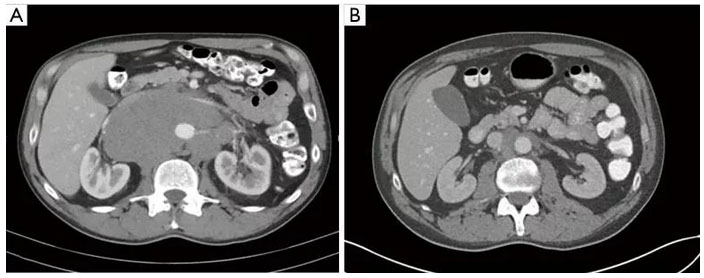

Ультразвуковое исследование/КТ, МРТ яичек/мошонки, органов малого таза и забрюшинного пространства. Это один из ключевых методов диагностики, который помогает не только обнаружить опухоль, но и оценить состояние лимфатических узлов в забрюшинном пространстве и органах брюшной полости, а также глубину инвазии злокачественного образования. Кроме того, он позволяет провести дифференциальную диагностику между герминогенными и негерминогенными опухолями. Если есть подозрения на метастазы, назначаются КТ и МРТ органов грудной клетки и головного мозга.